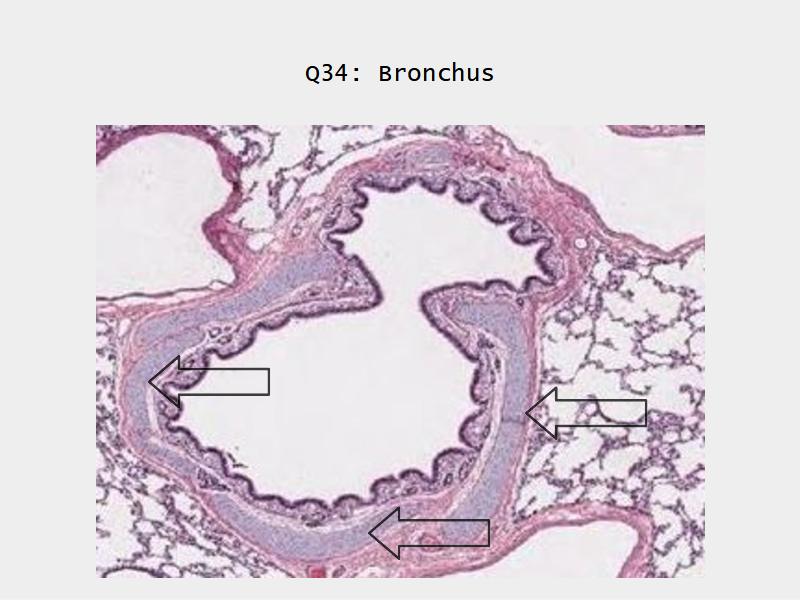

Bronchi - Transitions

- Intrapulmonary bronchi

- Irregular cartilage

- Respiratory epithelium

- Glands